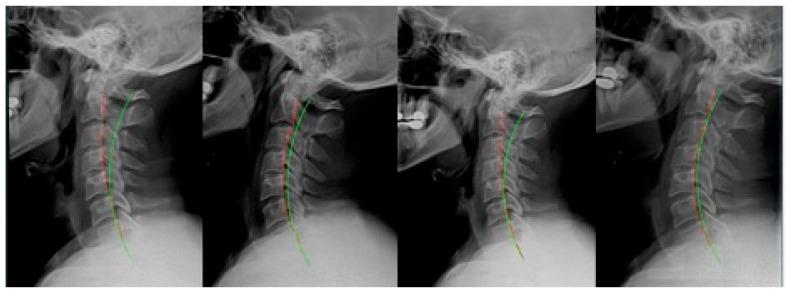

This series illustrates how rear-end impact motor vehicle collisions (MVCs) alter the cervical spine's alignment and demonstrates therapeutic use of cervical extension traction to improve lordotic alignment and other outcomes. This is a retrospective reporting of 7 adult patients (4 males and 3 females, 28-42 years) treated for cervical hypolordosis. These subjects received Chiropractic BioPhysics (CBP) rehabilitation and then were involved in a rear-end MVC. All cases had radiographic assessment that quantified the buckling of the cervical spine, presumably resulting directly from the CAD trauma. After an average of 3 years and 9 months (range: 1-7.6 years) following their initial program of care, the 7 patients sought care for a second time after the MVC. At this time, compared with their previously recorded post-treatment spine radiographs, there was an average 18.7° (range: 7.6-35.4°) reduction in cervical lordosis, a 9.2 mm (range: 3.6-19.8 mm) increase in anterior head translation (AHT), an 11.3° (range: 0.2-19.9°) decrease in the atlas plane line (APL), as well as a 35.7% (range: 22-52%) average neck disability index score (NDI) measured after the MVC. After the crash, a second round of CBP rehabilitation was administered, resulting in an average 15.1° improvement in cervical lordosis, 10.9 mm reduction in AHT, 10.4° increase in APL, and a 23.7% drop in NDI after an average of 35 treatments over 9 weeks. Treatment was universally successful, as an average 80% re-establishment of the lordosis toward its pre-injury state was found. There were no adverse events reported. This case series demonstrates that motor vehicle collisions may alter the alignment of the cervical spine. Rehabilitation of the cervical curve using extension traction improved the patients' initial pre-crash alignments toward their pre-injury alignments and was likely responsible for improvement in the patients' conditions. Clinical trials are needed to confirm these findings.

本系列阐述了机动车追尾碰撞(MVCs)如何改变颈椎排列,并展示了颈椎伸展牵引在改善前凸排列及其他结果方面的治疗用途。这是一项对7例因颈椎前凸不足接受治疗的成年患者(4例男性和3例女性,年龄28 - 42岁)的回顾性报告。这些受试者接受了脊椎矫正生物物理学(CBP)康复治疗,随后遭遇了机动车追尾碰撞。所有病例均进行了影像学评估,量化了颈椎的屈曲情况,推测这是由追尾创伤直接导致的。在其初始治疗方案实施平均3年9个月(范围:1 - 7.6年)后,这7例患者在追尾碰撞后再次寻求治疗。此时,与之前记录的治疗后脊柱X光片相比,颈椎前凸平均减少了18.7°(范围:7.6 - 35.4°),头部向前平移(AHT)增加了9.2毫米(范围:3.6 - 19.8毫米),寰椎平面线(APL)减少了11.3°(范围:0.2 - 19.9°),并且追尾碰撞后测量的颈部残疾指数(NDI)平均得分增加了35.7%(范围:22 - 52%)。碰撞后,进行了第二轮CBP康复治疗,在9周内平均进行35次治疗后,颈椎前凸平均改善了15.1°,AHT减少了10.9毫米,APL增加了10.4°,NDI下降了23.7%。治疗普遍成功,因为发现前凸平均恢复到损伤前状态的80%。未报告不良事件。该病例系列表明机动车碰撞可能会改变颈椎排列。使用伸展牵引对颈椎曲度进行康复治疗,使患者从碰撞后的初始排列改善至损伤前的排列,这可能是患者病情改善的原因。需要进行临床试验来证实这些发现。